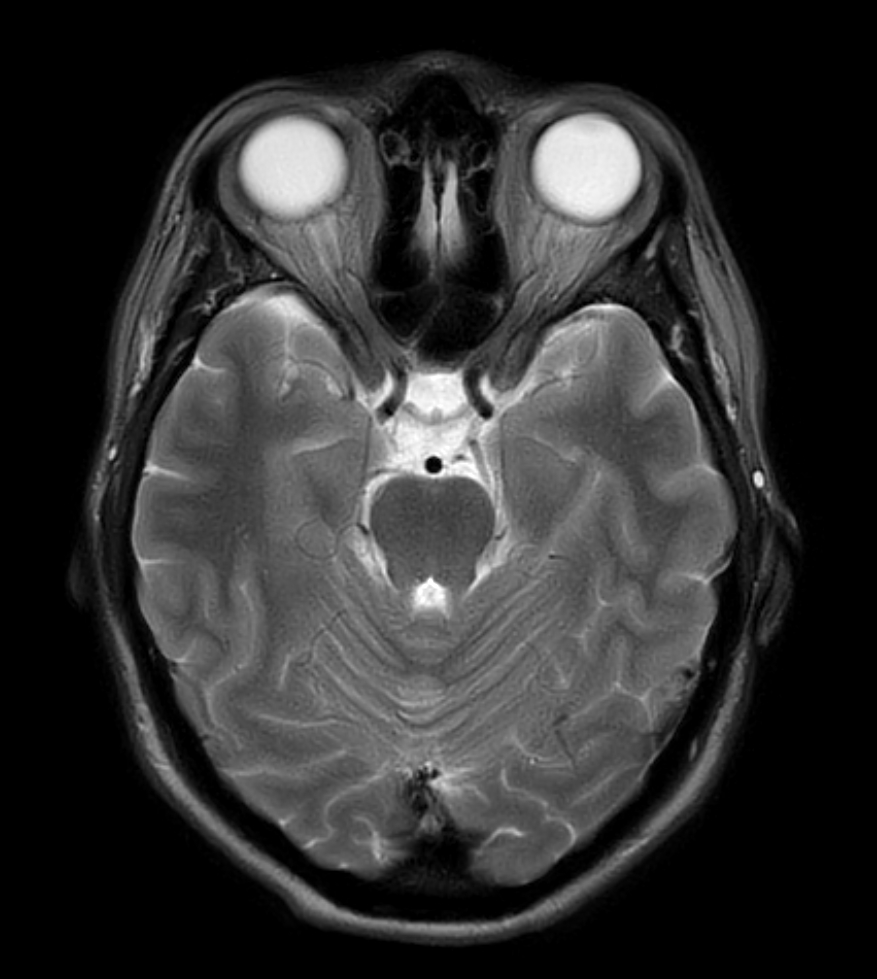

T2w TSE - mDIXON XD (In Phase)